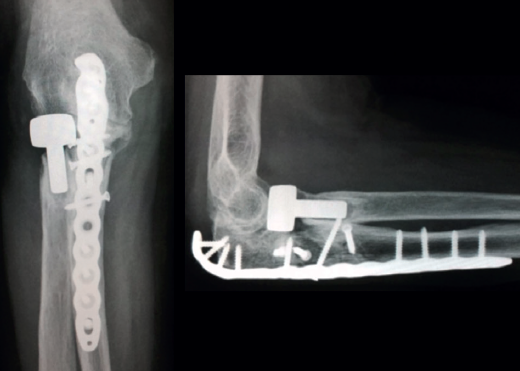

Las placas colocadas en la superficie posterior del cúbito son el sistema de fijación recomendado, proporcionando una fijación más resistente que los cerclajes con agujas de Kirschner y además permiten la fijación adicional de los fragmentos óseos y de la coronoides con tornillos o placas ortogonales en las superficies medial o lateral en los casos con gran conminución metafisaria(1,2,17). Las placas especialmente diseñadas de olécranon (Figuras 5 y 6) o las placas de compresión dinámica de contacto limitado (LC-DCP) de 3,5 mm conformadas para adaptarse a la morfología del cúbito son preferibles a las placas semitubulares, al aportar una fijación más estable(2,18,19).

Cuando la fractura del olécranon incluye una fractura de la coronoides, la reducción y la fijación de esta es condición imperativa para conseguir la estabilidad humerocubital (Figuras 7, 8 y 9). La reducción puede llevarse a cabo a través de la fractura del olécranon o por medio de un abordaje medial, separando o a través de la musculatura flexora/pronadora, teniendo identificados y protegidos el nervio cubital y el fascículo anterior del ligamento colateral medial. En los casos en los que es necesario realizar la sustitución de la cabeza del radio por una prótesis, también es posible el acceso lateral a la fractura de la coronoides. En general, el fragmento permite la fijación con tornillos desde posterior a anterior, a través de la placa posterior o independientes de esta, o en ocasiones desde anterior a posterior. La utilización de placas de 2,7 mm o específicas de coronoides, y técnicas de suturas no reabsorbibles atadas sobre el cúbito proximal o sobre la placa de fijación del cúbito son otras opciones(13,17). Para los grandes defectos óseos o fracturas irreconstruibles de la coronoides, se han descrito injertos óseos de la cresta ilíaca e injertos osteocondrales de la cabeza del radio con resultados impredecibles debido a la osificación heterotópica y a la reabsorción ósea del injerto(20,21).

Las fracturas complejas del cúbito que afectan al olécranon o a la coronoides pueden fijarse de “proximal a distal”(1) o de “distal a proximal”(22) en función de lo que resulte más fácil en cada caso. En la fijación de “proximal a distal”, el fragmento proximal del olécranon se fija temporalmente a la tróclea con una o varias agujas de Kirschner de 1,5 mm y el cúbito se reduce sobre el fragmento de olécranon proximal. La fijación de “distal a proximal” se centra inicialmente en la reducción y la fijación de los fragmentos distales del cúbito con objeto de simplificar los trazos de fractura y finalmente proceder a la reducción y la fijación con el fragmento proximal del olécranon. En la reconstrucción de la escotadura mayor del olécranon, se deben tener en cuenta la relación anatómica normal de la coronoides con el olécranon y la existencia de la zona desprovista de cartílago en la escotadura mayor. La incongruencia articular en las fracturas conminutas tiene menos impacto en el resultado clínico que la falta de alineación, altura y rotación de la escotadura mayor del olécranon(1).